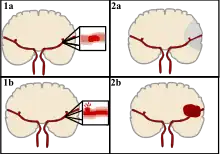

Stroke can be classified into two major categories: ischemic and hemorrhagic.[20] Ischemic stroke is caused by interruption of the blood supply to the brain, while hemorrhagic stroke results from the rupture of a blood vessel or an abnormal vascular structure.

About 87% of stroke is ischemic, with the rest being hemorrhagic. Bleeding can develop inside areas of ischemia, a condition known as "hemorrhagic transformation." It is unknown how many cases of hemorrhagic stroke actually start as ischemic stroke.[2]

Hemorrhagic

There are two main types of hemorrhagic stroke:[30][31]

- Intracerebral hemorrhage, which is bleeding within the brain itself (when an artery in the brain bursts, flooding the surrounding tissue with blood), due to either intraparenchymal hemorrhage (bleeding within the brain tissue) or intraventricular hemorrhage (bleeding within the brain's ventricular system).

- Subarachnoid hemorrhage, which is bleeding that occurs outside of the brain tissue but still within the skull, and precisely between the arachnoid mater and pia mater (the delicate innermost layer of the three layers of the meninges that surround the brain).